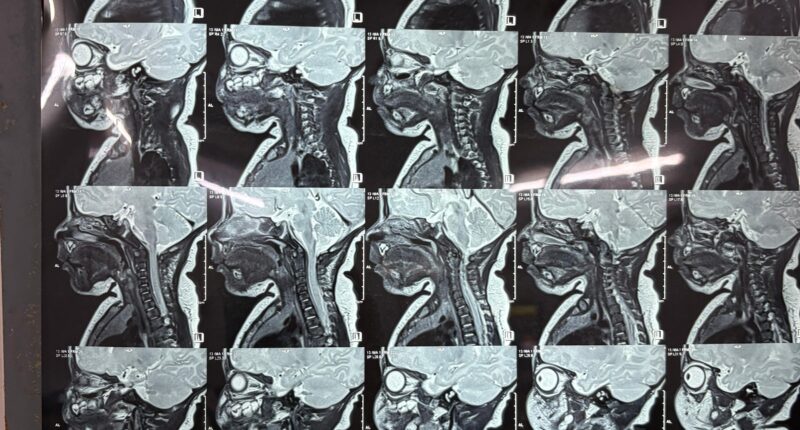

Following the delivery, doctors at the hospital referred the newborn to renowned paediatric surgeon Dr. Aniruddha Basak for specialised evaluation. When the baby was just 17 days old, Dr. Basak recommended a series of diagnostic tests to determine the severity of the condition. During this period, the cyst began to enlarge at an unusual and alarming rate, leaving the parents deeply worried and prompting an urgent return to the specialist with the test results.

The infant was admitted on November 21, and after thorough assessment, stabilisation, and preparation, the surgical team scheduled the operation for November 25. The delicate procedure lasted two hours and was carried out with precision, resulting in a successful outcome without any complications—an extraordinary feat considering the age of the patient and the technical challenges involved.